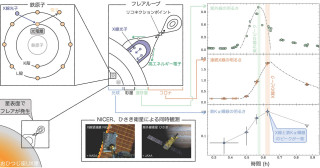

近年、磁気共鳴画像(MRI)法などの非侵襲的な医用画像法やコンピュータ技術の発展により、ヒトと近縁な霊長類を比較して、ヒトの脳の進化的な共通性や多様性を解明し、精神・神経疾患の病態の理解や予測の実現をめざす霊長類比較脳イメージングが注目されています。日本では、「革新的技術による脳機能ネットワークの全容解明プロジェクト」で、非ヒト霊長類モデルの脳画像データベースの開発が進んでいます。最近では、本プロジェクトから小型霊長類のマーモセットの脳画像データベースが公開されました(https://dataportal.brainminds.jp/marmoset-mri-na216)。

本プロジェクトおよび戦略的国際脳科学研究推進プログラムとの連携体制をもつ本研究グループは、世界最大級の霊長類脳標本コレクションを対象に、超高磁場MRI装置を用いて、脳標本を切り出すことなく神経線維の連絡性を可視化した拡散テンソル画像(diffusion tensor imaging; DTI画像)を撮像する顕微鏡的MRI技術を開発し、体重100gほどのマーモセットから体重38㎏のチンパンジーにまでわたる霊長類種の神経回路の多様性を全脳レベルで描出することに成功しました。本脳画像リポジトリは、今回の発表論文で第2フェーズへと入り、さらに、多様な霊長類の脳情報を包括的に提供することで、データ駆動型科学を通したヒト脳の特徴や精神・神経疾患の解明に貢献しています。